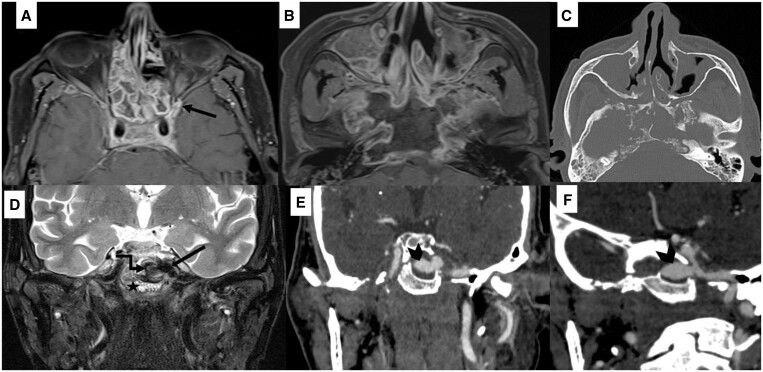

The coronavirus pandemic is now a public health emergency and has spread to nearly 206 countries across the globe. This novel disease has shaken the psycho-social, economic, and medical infrastructure of India. This has become even more challenging, considering the country's huge population. With the increase in the number of coronavirus disease (COVID) cases, our country has seen an unforeseen, unprecedented rise in a potential life and organ-threatening disease-mucormycosis. Mucormycosis is a deadly, extremely morbid, possibly life-threatening, and most feared complication of the coronavirus, caused by environmental molds belonging to the order Mucorales. Here, we report 2 cases of massive epistaxis due to internal carotid artery (ICA) pseudoaneurysm secondary to mucormycosis, post-COVID-19 pneumonia, which was managed by the endovascular route. To the best of our knowledge, there is very sparse literature available describing endovascular treatment of intracranial ICA pseudoaneurysm in a patient with COVID-induced mucormycosis.